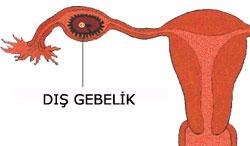

- Dış gebelik (ektopik gebelik) tedavisinde uygulanan başlıca iki yöntem vardır.